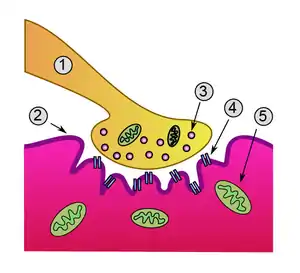

神经肌肉接点(英文:Neuromuscular junction)又称神经肌肉接头[1]、神經肌肉會合處[2],是传出神经纤维末梢与肌肉纖維之间形成的突触性连接,也是化学联络点,与神经元之间的突触功能相同[3][4][5]。

神经纤维分为许多末梢分支,每个分支嵌入肌细胞膜上称为運動终板的凹陷中,因此“突触前膜”为运动神经末梢,“突触后膜”为肌纤维局部膨大形成的运动终板;运动终板内容纳数以千计的受体(长形的蛋白质分子,形成穿过膜的通道)。当运动神经电兴奋促使前膜释放神经递质,神经递质与终板上受体结合,就可实现横纹肌的兴奋收缩。